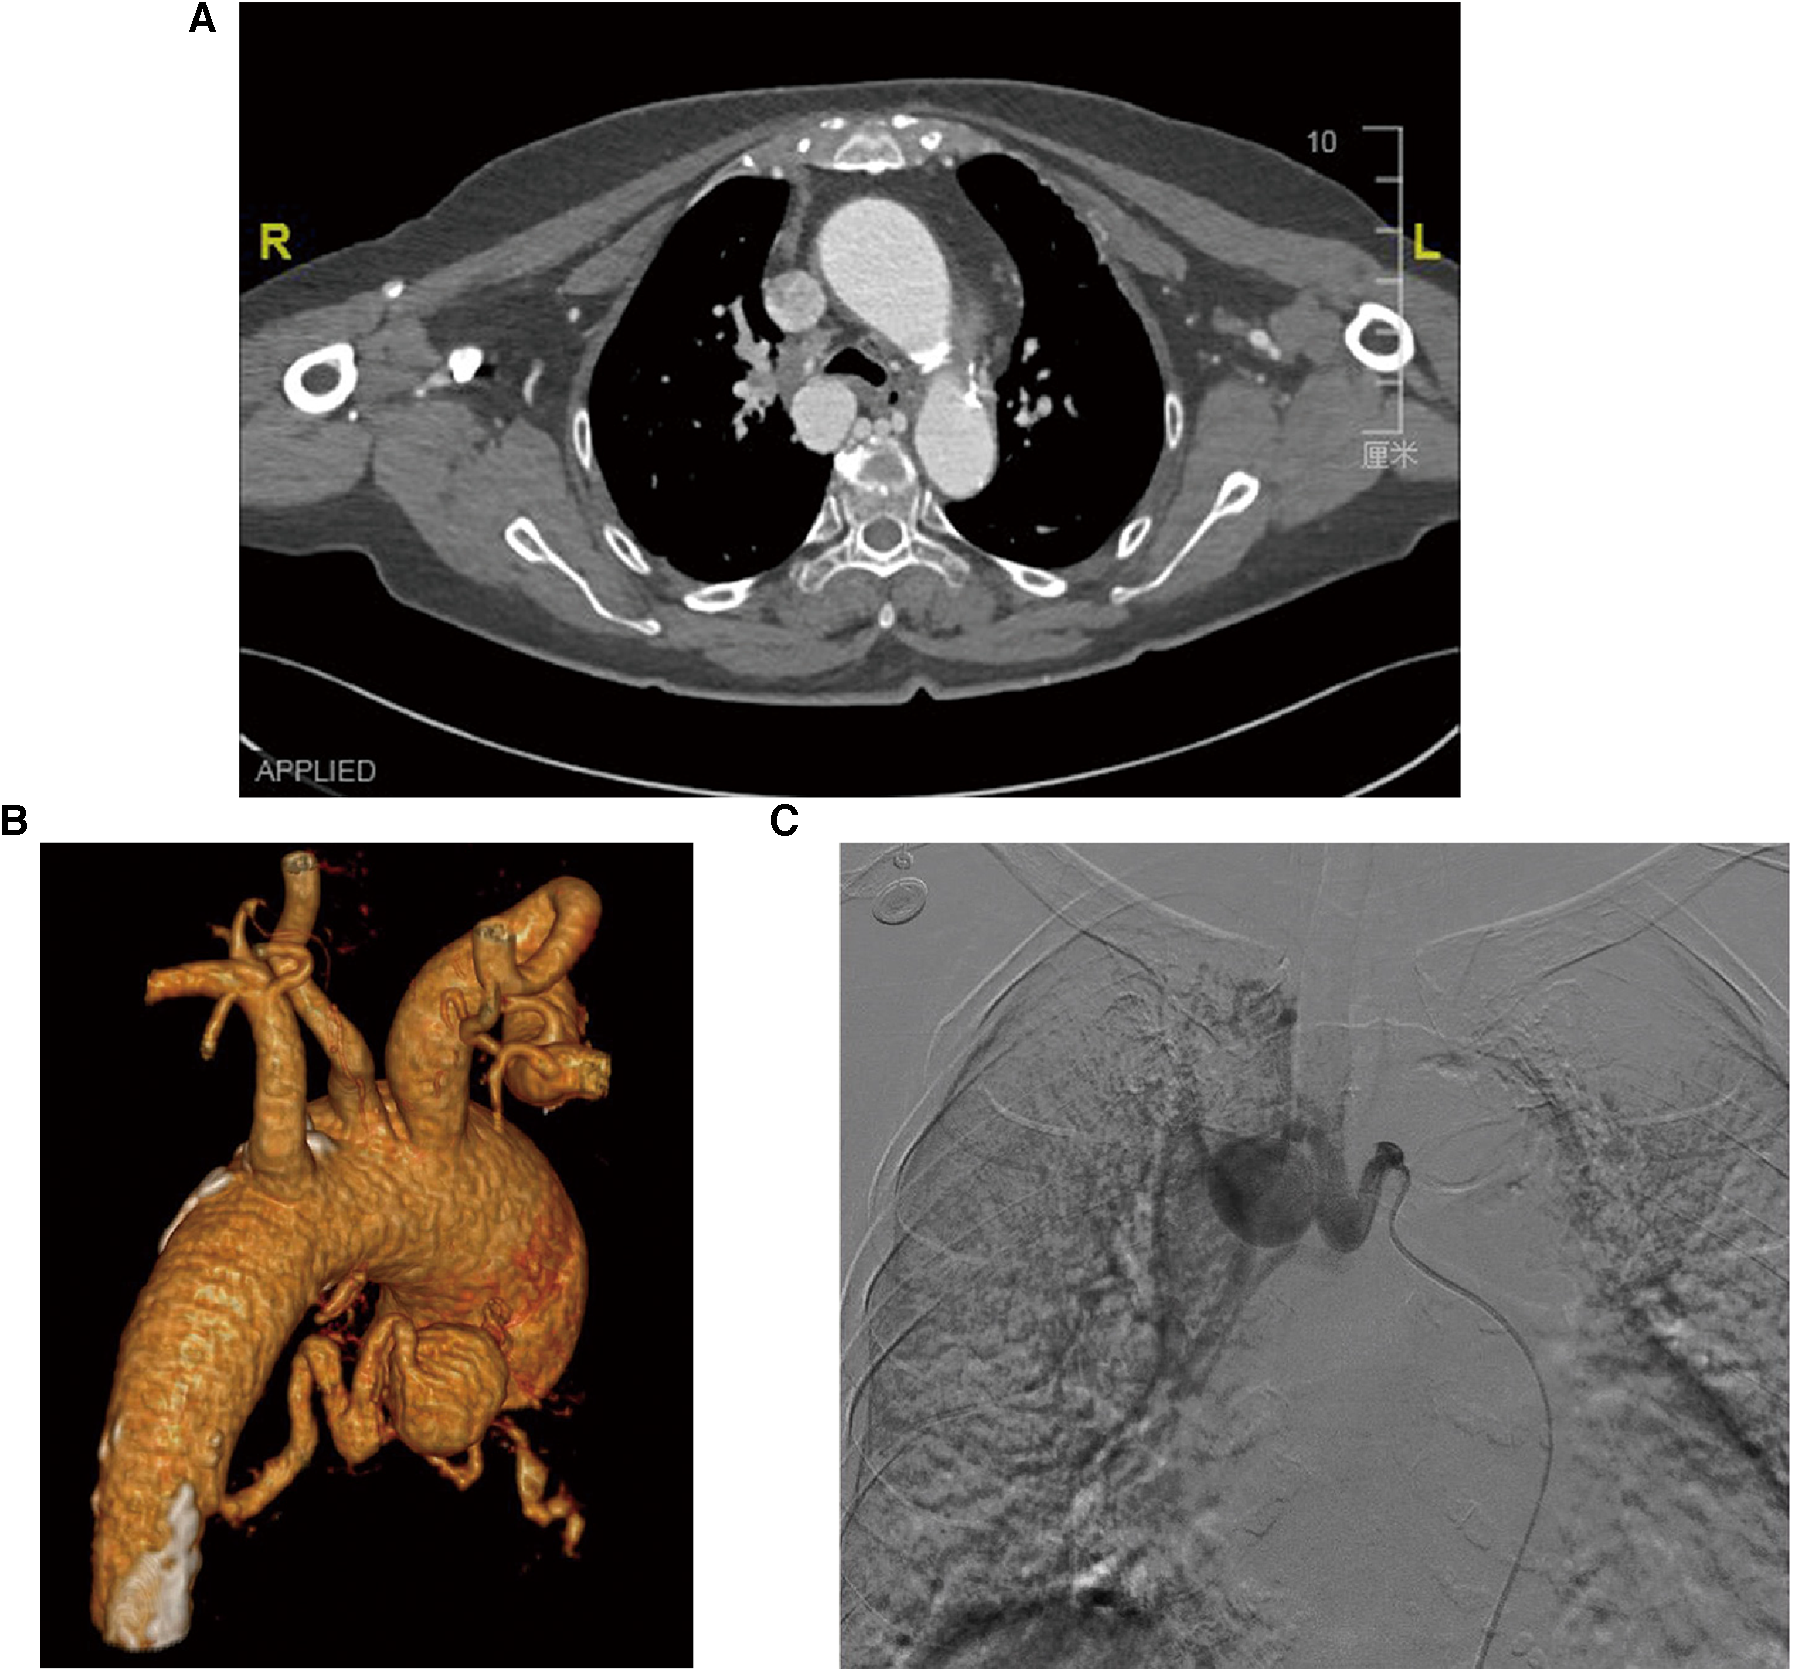

The suspicion of an aneurysm was first raised by an abnormal enhancement of a mediastinal lesion on a contrast-enhanced computed tomography (CT) scan of the chest (Figure 1A). The subsequent three-dimensional reconstruction of the CT angiogram showed a BAA with a 25-mm diameter and a dilated and tortuous inflow vessel from the right bronchial artery trunk (Figure 1B), which together with an aortic arch angiogram confirmed this diagnosis (Figure 1C).

Figure 1

Diagnostic images of the patient with BAA. (A) The CT scan image of the chest shows an abnormally enhanced lesion in the mediastinum and dilated bronchial arteries near the descending aorta, but no entrapment or hemopneumothorax. (B) Three-dimensional reconstruction of the CT angiographic model shows a 25-mm-diameter BAA from the descending aorta with a dilated and tortuous inflow vessel. (C) Selective bronchial arteriography shows that the aneurysm was fed by a bronchial artery dilated by the descending aorta.